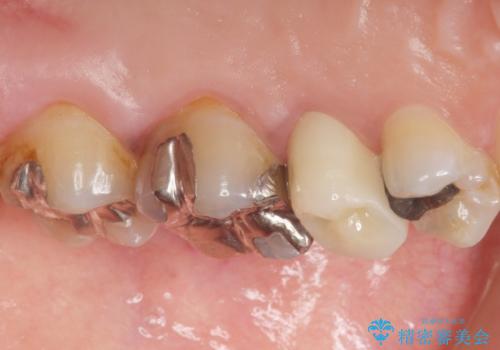

根管治療後、セラミッククラウンによる補綴を行いました。

根管治療により症状がなくなり、またセラミッククラウンの自然な仕上がりにご満足頂けました。

クラウンの種類:オールセラミッククラウン スタンダード